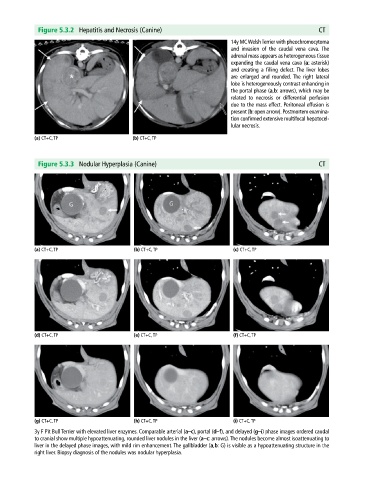

Figure 5.3.2 Hepatitis and Necrosis (Canine) CT

14y MC Welsh Terrier with pheochromocytoma

and invasion of the caudal vena cava. The

adrenal mass appears as heterogeneous tissue

expanding the caudal vena cava (a: asterisk)

and creating a filling defect. The liver lobes

are enlarged and rounded. The right lateral

lobe is heterogeneously contrast enhancing in

the portal phase (a,b: arrows), which may be

related to necrosis or differential perfusion

due to the mass effect. Peritoneal effusion is

present (b: open arrow). Post mortem examina-

tion confirmed extensive multifocal hepatocel-

lular necrosis.

(a) CT+C, TP (b) CT+C, TP

Figure 5.3.3 Nodular Hyperplasia (Canine) CT

3y F Pit Bull Terrier with elevated liver enzymes. Comparable arterial (a–c), portal (d–f), and delayed (g–i) phase images ordered caudal

to cranial show multiple hypoattenuating, rounded liver nodules in the liver (a–c: arrows). The nodules become almost isoattenuating to

liver in the delayed phase images, with mild rim enhancement. The gallbladder (a,b: G) is visible as a hypoattenuating structure in the

right liver. Biopsy diagnosis of the nodules was nodular hyperplasia.